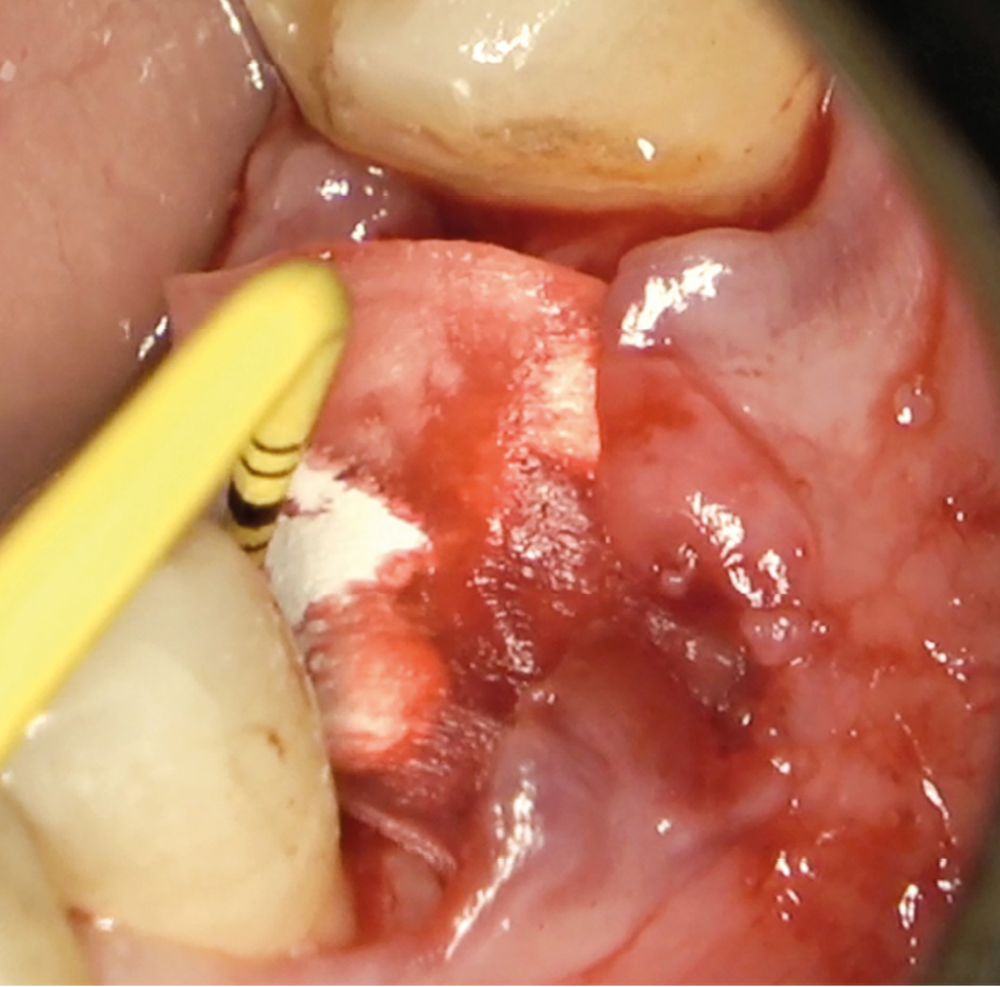

- Avulsion de la 36 et régénération osseuse guidée (ROG) réalisée en 2017 suite à une fracture de la dent et une infection

Chez ce patient, le traitement de la péri-implantite a comporté une chirurgie associant décontamination électrolytique de la surface implantaire, régénération osseuse guidée et enfouissement de l’implant. Le résultat à 2 ans est très moyen au vu du pourcentage de régénération osseuse obtenu. Comment peut-on prévoir un tel résultat alors que l’on a suivi les recommandations à la lettre, que l’on a utilisé les dernières technologies de décontamination, que l’on y a mis tous les moyens, que le patient est en bonne santé générale et qu’il vient en plus régulièrement aux séances de thérapeutique de soutien ? Le succès du traitement des péri-implantites n’est pas simple à obtenir, surtout quand un élément clé est compromis… la maintenance personnelle ! En effet le succès n’est possible que si le contrôle de plaque quotidien est optimal et, ici, ça n’était pas le cas. Le patient se brossait certes les dents, mais ne passait pas quotidiennement les brossettes, ce qui…